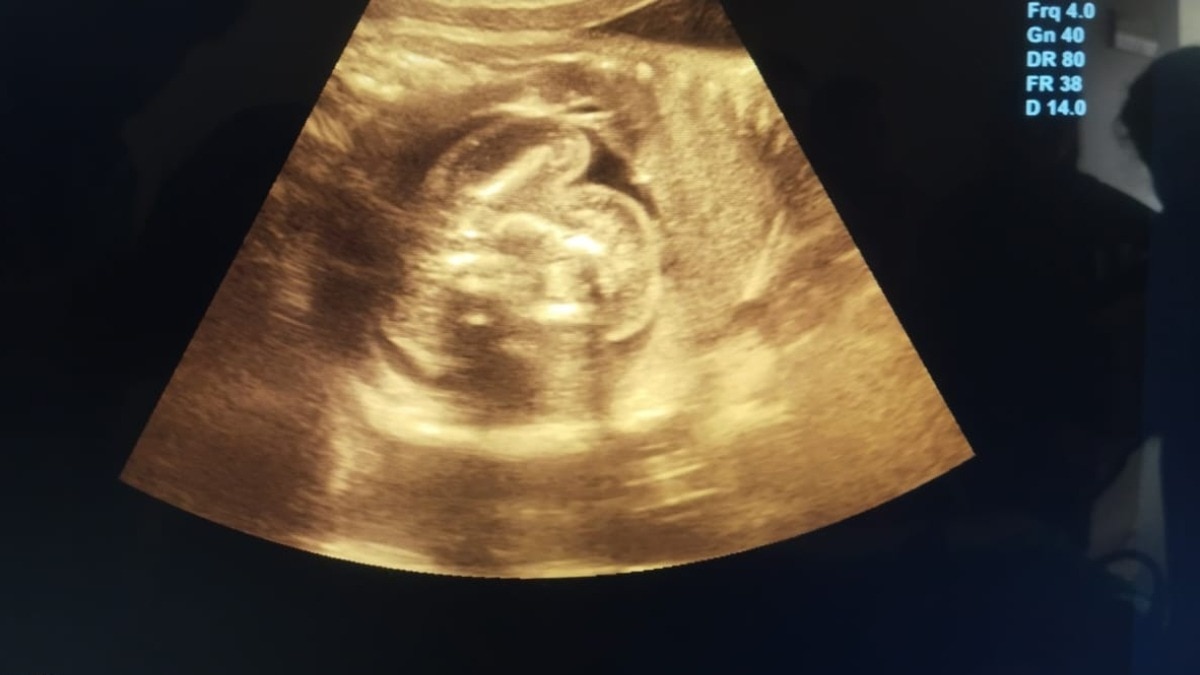

Emma’s pregnancy had progressed without complications. Regular checkups, ultrasounds, and prenatal care showed no signs of irregularities. So when her labor began two weeks before her expected due date, she and her husband, Mark, weren’t particularly concerned.

Upon arriving at the hospital, Emma was admitted for monitoring. While reviewing her latest ultrasound, doctors noticed something unusual: a second, smaller amniotic sac adjacent to the main one. Confused and intrigued, the medical team prepared for what they assumed was an unusual presentation of twins.

As the delivery began, doctors carefully navigated the birth of Emma’s healthy baby girl. However, what followed next left the entire team stunned. Inside the secondary sac was what appeared to be an underdeveloped fetus that had stopped growing early in gestation.

This rare occurrence, known in medical terms as “fetus in fetu,” happens when a twin embryo is enveloped by its sibling during the early stages of pregnancy. The enveloped fetus does not develop fully and typically remains undetected unless it causes complications or is discovered incidentally.

However, in Emma’s case, the discovery happened at birth, making it even more uncommon. The encapsulated fetus had its own amniotic sac and had stopped developing several months into the pregnancy. It posed no risk to Emma or her baby and was removed safely during the delivery procedure.

Ultrasound technology has come a long way over the past two decades. Today’s machines offer high-resolution, real-time imaging that allows obstetricians to monitor fetal development with incredible detail. Even so, some anomalies may go unnoticed, especially if they do not present as a health risk.